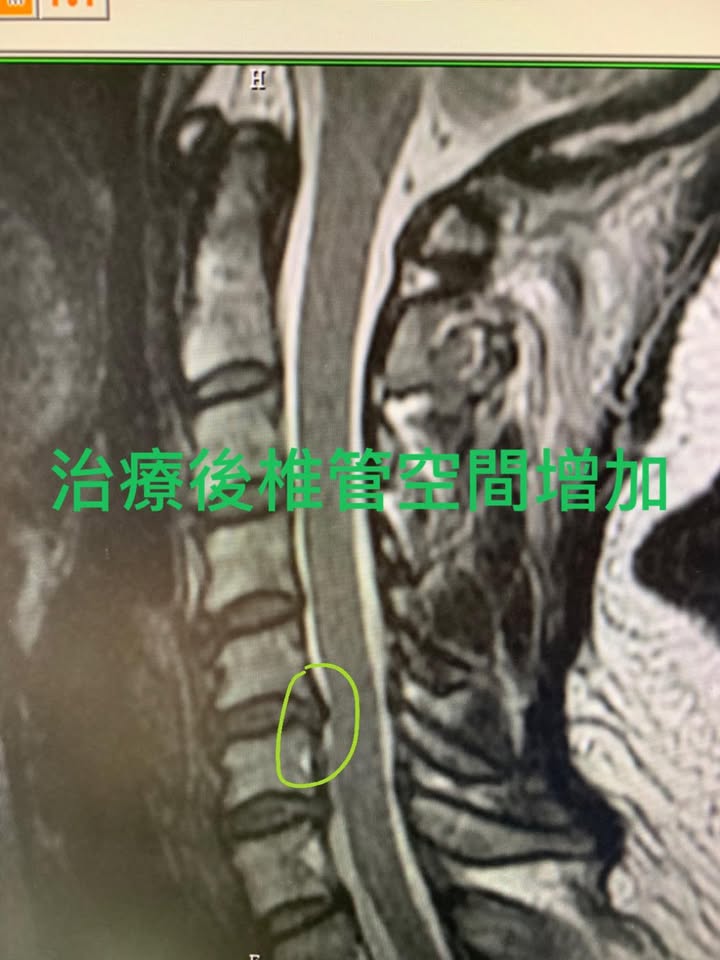

😢😢四十多歲的陳小姐右邊頸痛連手臂,慢性疼痛快兩年,這半年開始惡化,右手臂刺痛不聽使喚,熱敷燙到也沒什們感覺,握力明顯下降,右手握不住一個馬克杯,在2017年底已經去醫院拍攝MRI(如圖),右邊頸椎壓迫明顯,x光片顯示頸椎過直,經過友人介紹來診所接受頸椎整合針刀醫學療法,高度懷疑神經根型頸椎病與輕微脊椎型頸椎病,😂這絕對是一個很難的案例,我告訴陳小姐如果一個月內沒看到效果就必須要開刀,而且不要拖延下去,我們非常幸運在前面三次治療就看到一些效果,陳小姐在接受一個療程八次後的治療後又去拍片複查(如圖)可以看到壓迫情況減少一些,椎管空間打開一些,重點是上述症狀幾乎完全改善,對冷熱的知覺回復,拿馬克杯不在會掉下去,握力明顯提升!!